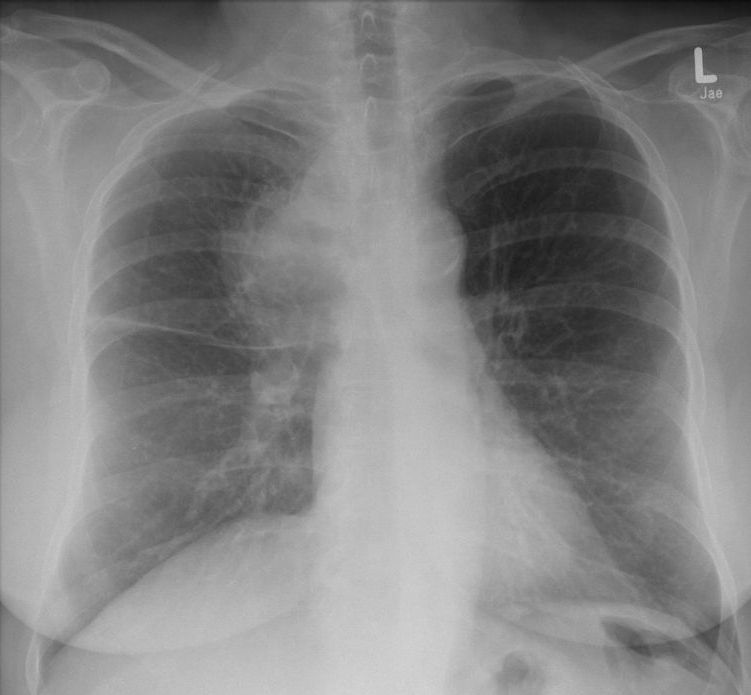

zentrales, kleinzelliges Lungenkarzinom rechter OL mit Infiltration des Mediastinums T4 N3 M1 oss ? 68jährige Patientin im reduzierten AZ und normalen EZ. Unsicherer Gang bei Kreislaufstörungen. Belastungsdyspnoe. Deutliche Leistungsschwäche. Supraklavikulargruben: links frei, rechts auffälliger Tastbefund. ![]() |

![]() |